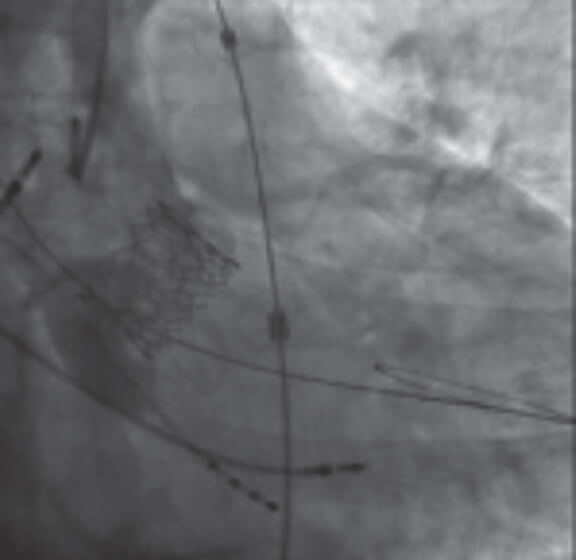

La válvula aórtica bicúspide (VAB) es el defecto valvular congénito más común. Se ha descrito en el 1-2% de la población general12. Es más frecuente en pacientes más jóvenes con EAo grave, aunque también se da en pacientes ancianos. Se asocia a un mayor estrés mecánico que predispone a calcificaciones y al desarrollo de EAo13. La estenosis de la VAB se considera todo un desafío anatómico para TAVI por estas razones: a) la forma del anillo suele ser extremadamente elíptica y tender a la dilatación aórtica comparado con la característica forma ovalada del anillo de la válvula aórtica tricúspide (VAT) que se asocia a fugas mucho mayores; b) la VAB suele tener un punto de coaptación de las cúspides más alto, lo cual puede ser un factor de confusión durante la intervención y aumentar el riesgo de embolización de la válvula (figura 1) y c) la distribución asimétrica del calcio tendente a formaciones voluminosas aumenta el riesgo de fuga periprotésica y rotura del anillo14. Todos estos elementos han de tenerse en cuenta a la hora de pensar en una intervención TAVI para pacientes con VAB ya que la mala aposición del stent es más habitual en pacientes con estas anomalías y se asocia a una incidencia más alta de insuficiencia periprotésica, disfunción valvular o degeneración precoz de la válvula implantada15.

Figura 1. Ejemplo de TAVI con balón expandible (Myval, Meril Lifesciences, India) en una estenosis aórtica bicúspide. La posición relativamente alta se debe al alto nivel de coaptación de los velos propio de las válvulas aórticas bicúspides.